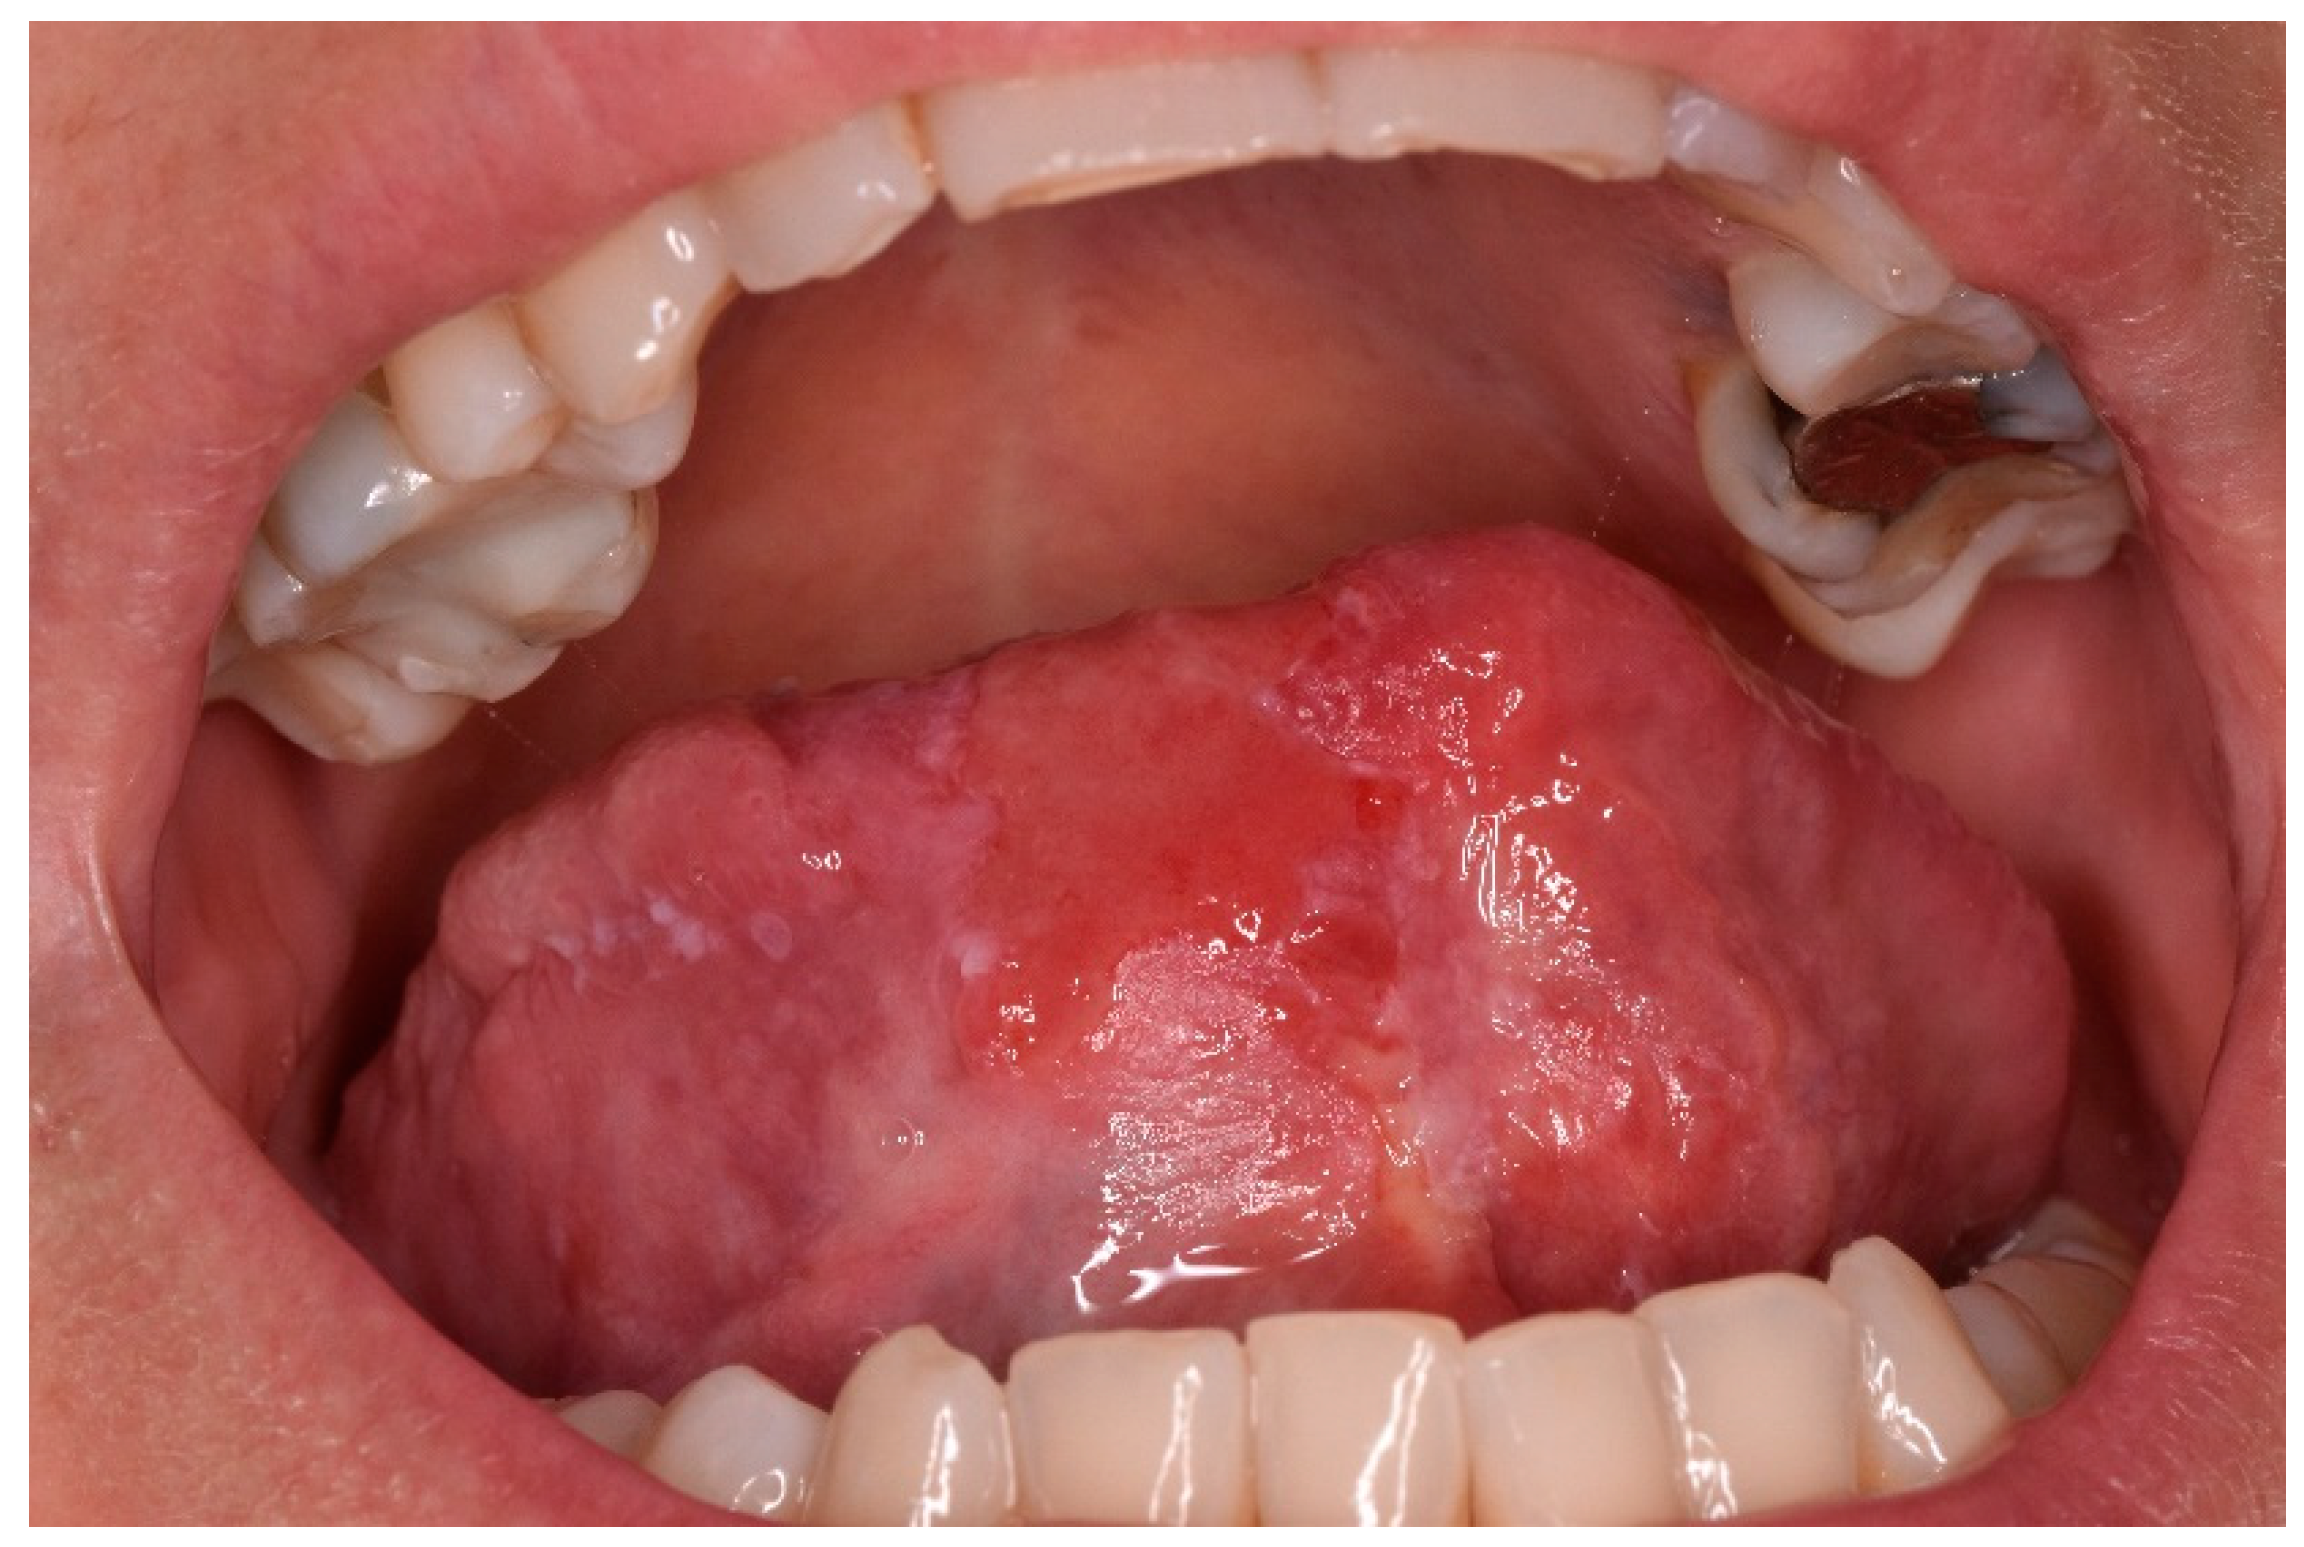

Plasma cell mucositis (PCM) is an unusual plasma cell proliferative disorder of the upper aerodigestive tract. It is a rare disease and its etiology is not yet known, it is considered a benign condition of adults and there is no correlation in literature with the development of plasma cell neoplasm. Clinical features are an intensely erythematous mucosa with papillomatous, cobblestone, nodular, or velvety surface changes. Symptoms include dysphagia, oral pain and pharyngitis [1]. Generally, PCM patients have a previous history of autoimmune or immunologically mediated disease. Despite plasma cell mucositis often involves the oral and genital mucosa, there was no genital involvement in this circumstance. We described a case of PCM involving the tongue of a 43-year-old-woman, the patient was referred to the Oral Pathology at the Faculty of Dentistry, Magna Graecia University of Catanzaro, in August 2019. Her past medical history was unremarkable. She reported a burning sensation in her mouth and local dysgeusia on the tip and the right lingual border for 5 years (Figure 1). In the first place several diagnostic hypotheses were proposed, the most of them discarded for incompatibility with blood and laboratory tests. The patient underwent an incisional biopsy under local anesthesia. The specimen was stored in a tube containing formalin 10% and sent to a laboratory for histopathological analysis. Microscopically, a large area of ulceration of the coating epithelium subtended by dense plasma cell infiltrate was observed. The final histopathological diagnosis was “Plasmacytosis of the mucous membranes with restriction for the kappa chains”. This disease rarely manifests itself on the tongue, especially in young patients with no comorbidities. The management of PCM is mainly aimed at reducing the symptoms, in fact the patient was treated with systemic prednisone 50 mg/day [2]. Many therapeutic treatments are able to stabilize but are not able to induce a complete remission. PCM is considered an uncommon benign disorder with a favorable prognosis. It is important to differentiate the PCM disease from other neoplastic conditions in order to achieve a better clinical management of the patients.

Figure 1. Ulcer localized on the tip of the tongue.